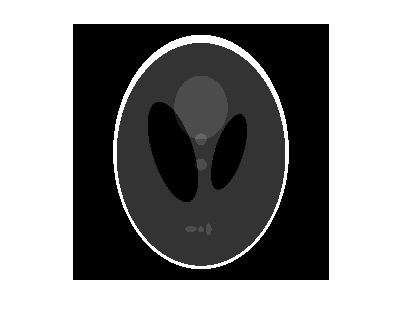

Сгенерируйте тестовое изображение и отобразите его. Тестовое изображение является фантомом главы Shepp-Логана, который может быть сгенерирован функцией phantom. Фантомное изображение иллюстрирует многие качества, которые найдены в реальной томографической обработке изображений человеческих голов.

P = phantom(256); imshow(P)